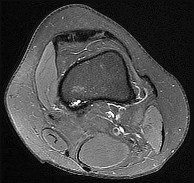

A 45-year-old female sustains a knee injury following a motor vehicle collision. Assuming the representative image demonstrates a medial tibial plateau fracture with articular depression (Schatzker IV), what is the most likely mechanism of injury?

A Schatzker IV fracture involves the medial tibial plateau. The medial plateau is structurally denser and stronger than the lateral plateau, meaning fractures here typically require higher energy. The classic mechanism is a varus force combined with an axial load. In contrast, lateral plateau fractures (Schatzker I-III) are typically caused by a valgus force with an axial load. High-energy trauma to the medial plateau is also highly associated with injury to the peroneal nerve, popliteal artery, and ligamentous structures (like the ACL or LCL).